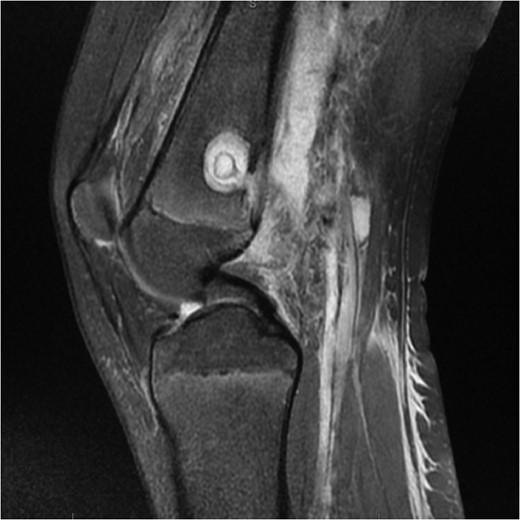

An X-ray, magnetic resonance imaging (MRI) and ultrasound scan was conducted (Fig 1, 2).

MRI Images on admission to Hospital. MRI images displaying ‘osteomyelitis with sequestration and erosion through the posterior cortex, extensively extending into the surrounding soft tissues’.

‘A large complex loculated abscess, 10 cm × 8 × 8 cm, extending between the muscles and extended to the posterolateral aspect of the distal femur. A cloaca is present in the cortical bone on the posterior aspect of the distal femur.’